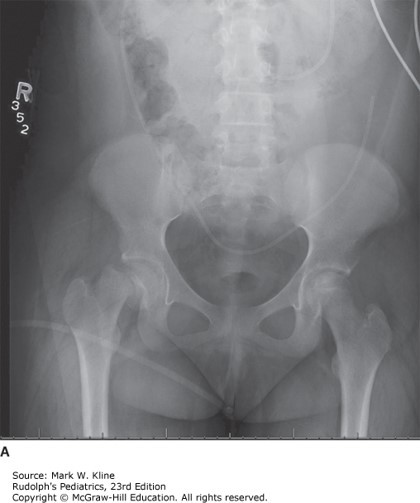

A 13-year-old boy is seen in the pediatrician's office for a 3-day history of pain in the right knee and a limp.

He reports the pain began as dull and deep in the right thigh, and that over the previous 2 days he began to have pain in the right knee and a limp on that side. He reports that he has been unable to participate in sports due to pain. Over-the-counter ibuprofen and acetaminophen have been minimally helpful. He has had no fever, nausea, vomiting, or trauma. He denies alcohol, drugs, or sexual activity. His past medical history is positive for mild hypertension noted on the previous year's well-child examination. On physical examination his height is 170 cm (5′7″), weight 100 kg (220 lb), and BMI 34.5 kg/m2. The right leg shows reduced internal rotation, reduced abduction, and reduced flexion. Upon flexion of the right hip the right thigh and leg rotate externally.

The correct answer is B

Slipped capital femoral epiphysis is a disease of unknown etiology and occurs typically in adolescents; the disorder is most common among obese boys with delayed skeletal maturation or in thin, tall adolescents having recently enjoyed a growth spurt. The onset of this disorder is frequently gradual; pain referred to the knee in 20% of cases can mask the hip pathology.

Photo: Kline MW. Rudolph's Pediatrics, 23e; 2018.